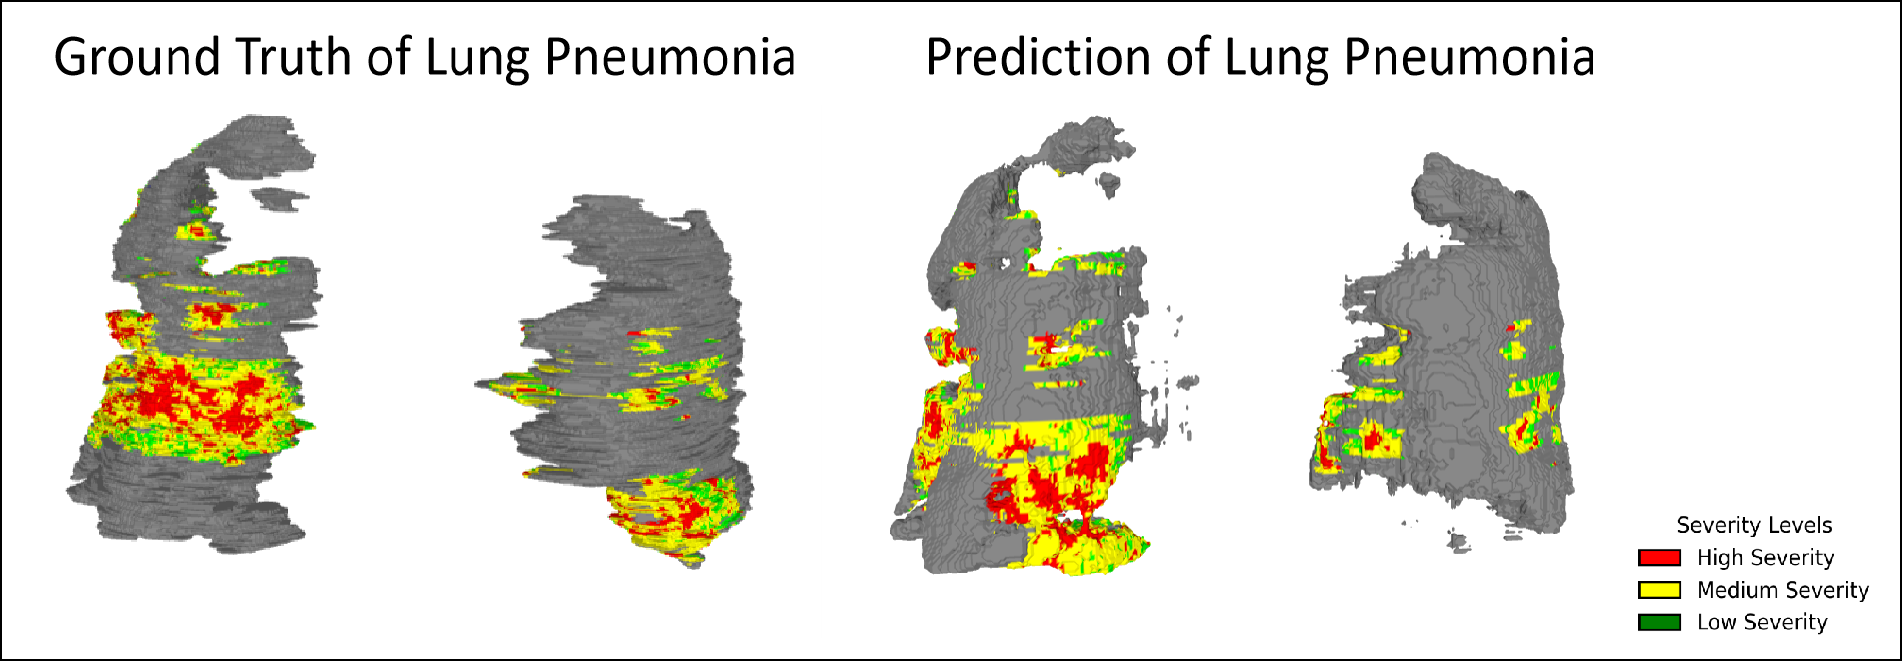

TARU-Net achieves strong performance across both lung cancer and COVID-19 pneumonia datasets:

TARU-Net achieves strong performance across both lung cancer and COVID-19 pneumonia datasets:

Color-coded severity: Red (severe), Yellow (moderate), Green (healthy tissue).

3D reconstructed predictions from TARU-Net for lung cancer cases.